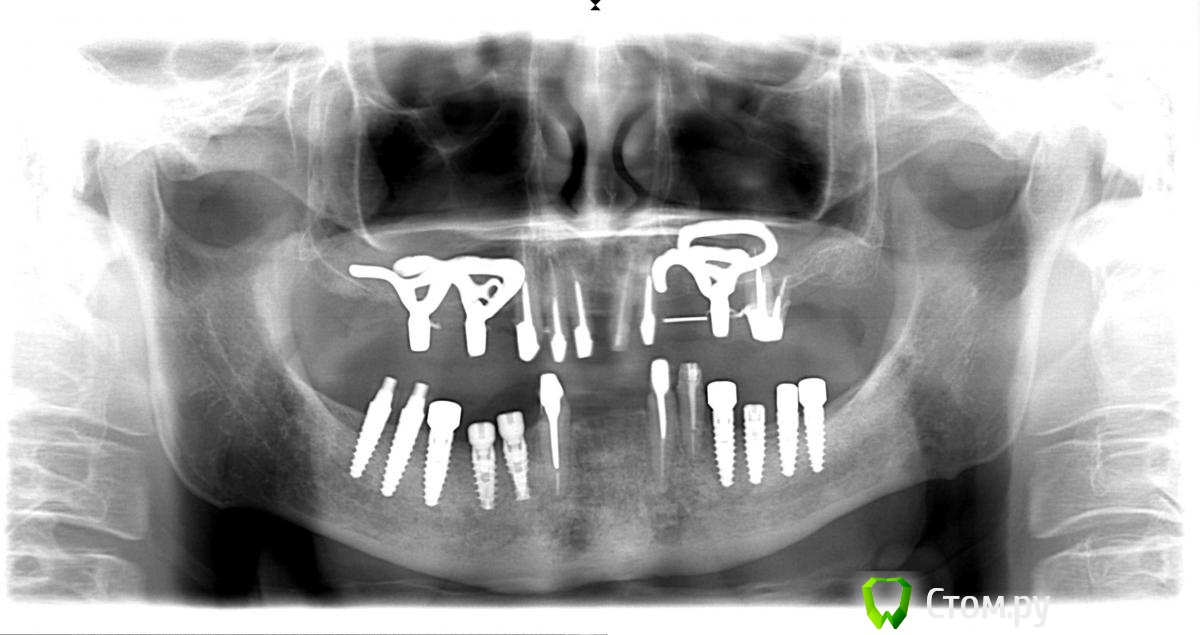

Troy Опубликовано 28 апреля, 2014 Поделиться Опубликовано 28 апреля, 2014 Вот такой рекольчик субпериостальников 5 лет прошло. Только камнями за НЧ кидать не надо . Это все таки моя глубокая молодость и за 5 лет мои взгляды сильно поменялись :). На синус пациент был категорически не согласен (интернет виноват),а хотел несъем2009 год2014 год. Жалоб нет. Так это выглядит сейчас. Ленты необнажены. Пардон за плохие фотки - фоткал на колегину мыльницуХотелось бы услышать Ваши комменты. 1 5 Ссылка на комментарий

red_butler Опубликовано 28 апреля, 2014 Поделиться Опубликовано 28 апреля, 2014 Да ну? Почему же?В третьем сегменте кость у имплантов ушла почти на 1/2, 2.7 удалять. Фото плохие, в Области 2.5 похоже свищ, резьба винтов тридцатой стороны выступает в полость рта и все в камнях. Мало? Ссылка на комментарий

Troy Опубликовано 28 апреля, 2014 Автор Поделиться Опубликовано 28 апреля, 2014 В третьем сегменте кость у имплантов ушла почти на 1/2, 2.7 удалять. Фото плохие, в Области 2.5 похоже свищ, резьба винтов тридцатой стороны выступает в полость рта и все в камнях. Мало?27 - его любимый зуб, он отказался его удалять еще 5 лет назад, пошли на поводу, пролечили покрыли, пока небеспокоит. В обл 25 свища нет, красное пятно артефакт на снимке фото плохие. Камней у него нет. Проблеммы в 3 сегменте действительно присутствуют. Но цель была показать СПИ.Извините что разачаровал .... :( А не новокузнецкие ли это "шедевры" ?Нет 1 1 Ссылка на комментарий

Mane Опубликовано 29 апреля, 2014 Поделиться Опубликовано 29 апреля, 2014 в третьем секторе еще до установки формирователя кость уже убежала от импланта?через 5 лет кость убежала везде 1 Ссылка на комментарий